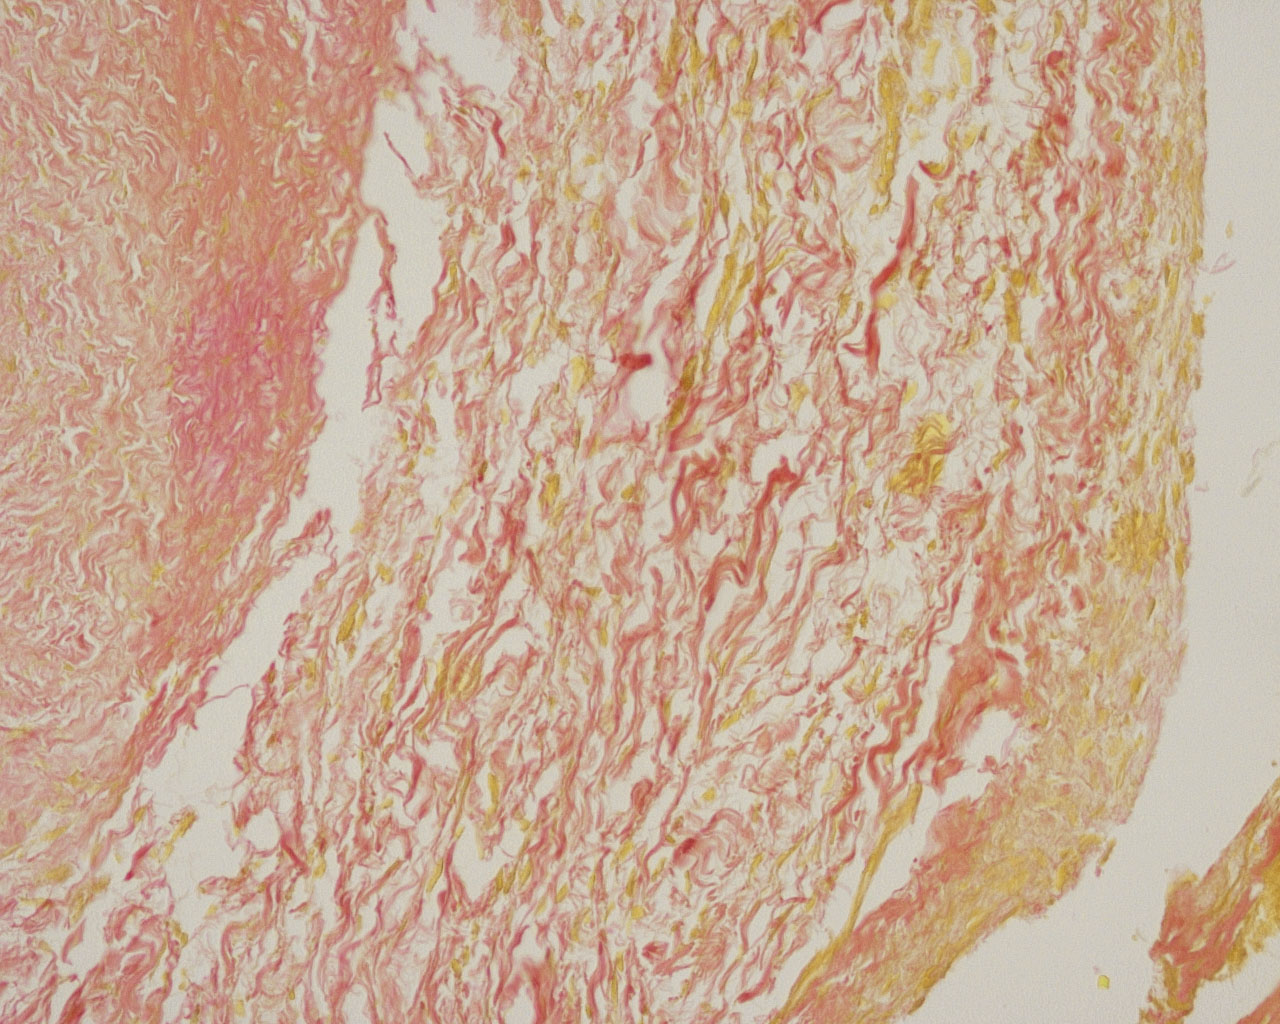

产品描述: 胶原纤维(Collagen Fiber)是结缔组织中分布最广含量最多的一种纤维,广泛分布于各种脏器,其中皮肤、巩膜、肌腱最丰富。Ⅰ型胶原纤维主要是骨、皮肤、肌腱纤维;Ⅱ型胶原纤维主要是软骨胶原;Ⅲ型胶原纤维主要在胚胎组织、成人血管、胃肠道;Ⅳ型胶原纤维主要在基膜中。Van Gieson胶原纤维染色原理与阴离子染料分子的大小和组织的渗透有关。分子的大小由分子量来体现,小分子量易穿透结构致密、渗透性低的组织,而大分子量则只能进入结构疏松的、渗透性高的组织。PA分子量小,丽春红和复红次之,淡绿分子量最大。VG染色后,肌纤维呈黄色,胶原纤维呈红色。 ![]() | |